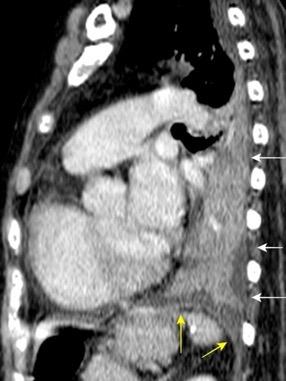

Diafragma “colgante” (“dangling sign”)

(“Dangling sign”)

TC. Mejor con multicorte. (reconstrucciones).

Asociación: Aire en pared.

Fracturas costal .Rotura esplénica. Neumoperitoneo.

Diafragma discontinúo Herniación de la grasa omental

Desser TS et al.The dangling diaphragm sign: sensitivity and comparison with existing CT signs of blunt traumatic diaphragmatic rupture. Emerg Radiol 2010